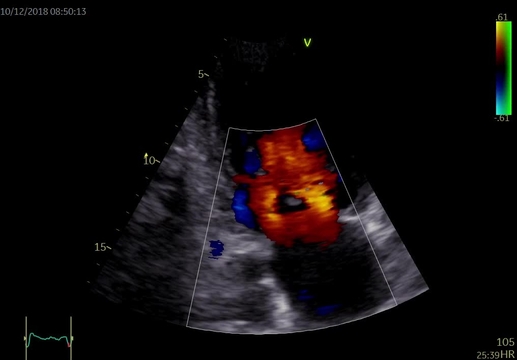

Při fyzikálním vyšetření měla nemocná TK 115/70 mm Hg, pravidelný puls 100/min, poslechově na plicích inspirační chrůpky při bázích a systolický šelest v prekordiu s maximem na hrotu, bez jasné propagace, intenzity 3/6. Dolní končetiny jsou se symetrickými perimaleolárními otoky, klidné varixy. Na EKG byla přítomna sinusová tachykardie 105/min, EKG kritéria hypertrofie levé komory s mírnými repolarizačními změnami, bez signifikantní ST denivelizace a abnormalita levé síně (obrázek 1). Echokardiografie prokázala dilataci a excentrickou hypertrofii levé komory (LVEDD 63 mm, LVMI 102 g/ m2, relativní tloušťka stěn 0,35), difúzní hypokinezi stěn výraznější v oblasti septa a těžkou systolickou dysfunkci levé komory s EF 24 %. Diastolická funkce měla charakter pseudonormalizace se zvýšenými plnicími tlaky levé komory (E/e'průměr 13). Dále byla zjištěna středně významná sekundární mitrální regurgitace 2–3+ při dilataci anulu a restrikci cípů v důsledku remodelace levé komory a sekundární trikuspidální regurgitace 2–3+ při dilataci anulu (video 1 a 2). Levá síň byla dilatována s indexovaným objemem 48 ml/m2 a zvýšena byla tenze v plicnici s odhadem PASP 49 mm Hg. Laboratorně prokázána elevace NT-proBNP 4 170 ng/l, mírná hypokalémie 3,6 mmol/l, kreatinin 112 μmol/l s mírně sníženou glomerulární filtrací 70 ml/min/1,73 m2 dle MDRD.

Video 1. Echokardiografické vyšetření, apikální čtyřdutinová projekce (1A) a dvoudutinová projekce (1B) – dilatace a významná systolická dysfunkce levé komory s EF 24 %

Video 2. Echokardiografické vyšetření – středně významná sekundární mitrální regurgitace 2–3+